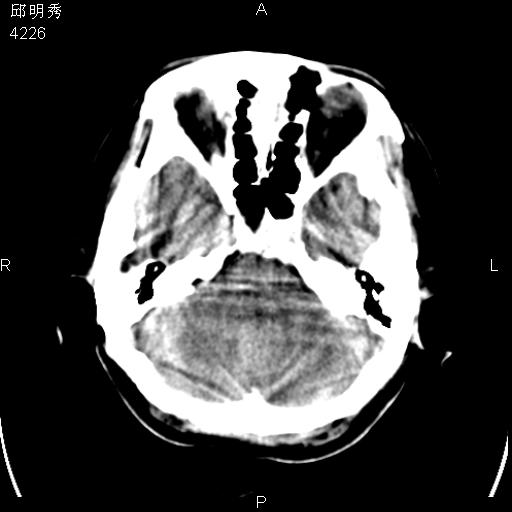

40f头晕十多天,右上肢麻木一天

脑白质变性或ms

脑白质脱髓鞘改变。

脑白质病;建议行mri检查。